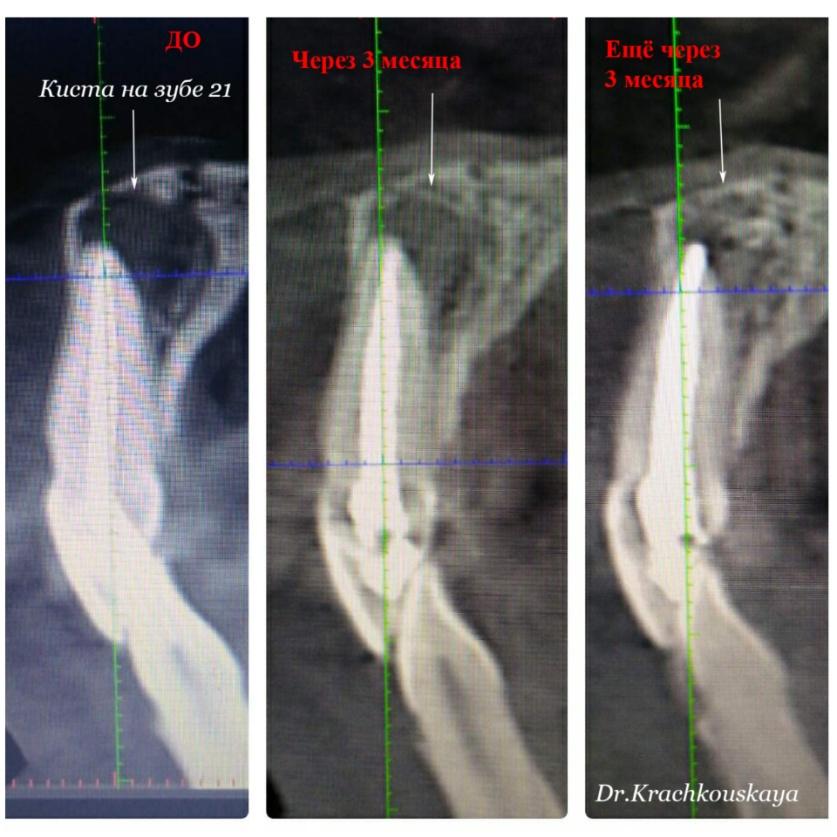

Konserwatywne leczenie torbieli korzeniowej (reendo – powtórne leczenie kanałowe).

Efekt po 6 miesiącach.

lek. stom. Anastazja Kraczkowska